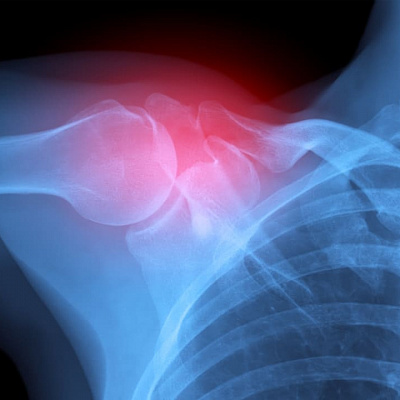

Посттравматический артроз

Посттравматический артроз — это хронический патологический процесс дегенеративного характера, для которого типично медленное, но неуклонное разрушение хряща. Как и следует из названия патологического состояния, оно развивается после перенесенной травмы или иного повреждения. Обычно на фоне внутрисуставных переломов, тяжелых вывихов, но не только. Порой причиной становятся расстройства и нарушения со стороны мягких тканей. Например, связочного аппарата конечности. В каждом конкретном случае требуется тщательная диагностика. Определение исходной причины нарушения, степени выраженности патологического процесса и прочих индивидуальных факторов.

Диагностика посттравматического артроза

- рентгенография;